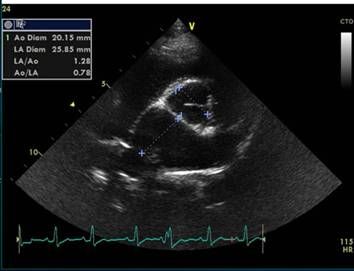

主动脉根部水平LA/AO

扫查方法

由肺动脉干水平,轻微后移,并抬高探头尾,探头光标指向位置不变

如图所示,RA右心房,LA左心房,LAA左心耳,RV右心室,PV肺动脉瓣,PT肺动脉干

图像要求

LA左心房、LAA左心耳呈现“鲸鱼征”

主动脉及三个主动脉瓣叶呈现“奔驰征”

右室流出道及肺动脉